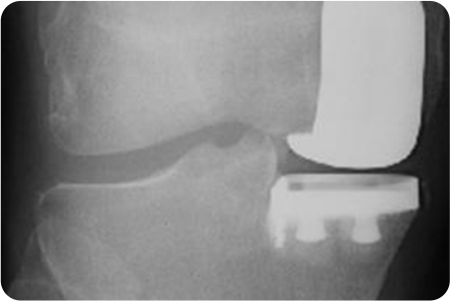

무릎 관절염

인공관절치환술

퇴행성 관절염으로 닳아버린 연골과 변형된

뼈 표면만을 정밀하게 절제합니다.

무릎의 굽힘·펴짐과 안정성을 고려해

인공관절을 삽입, 무릎 중심축을 바로 잡아줍니다.